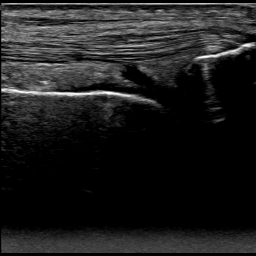

Figure 8 shows two US images that have been correctly classified by both approaches and that are relatively easy to classify by medical experts. Figure 8a shows an US image where the femur, the patella and the SQR are clearly visible, and the SQR is thin (i.e., not distended). On the other hand, Figure 8b shows an example of a Distended SQR. In this case, the SQR is clearly thick and hence distended.

Refer to caption

(a) Non-Distended SQR

(b) Distended SQR

Figure 8: Examples of images correctly classified by both solutions. The purple arrow points to the femur, the orange arrow points to the patella, and the green box indicates the SQR.